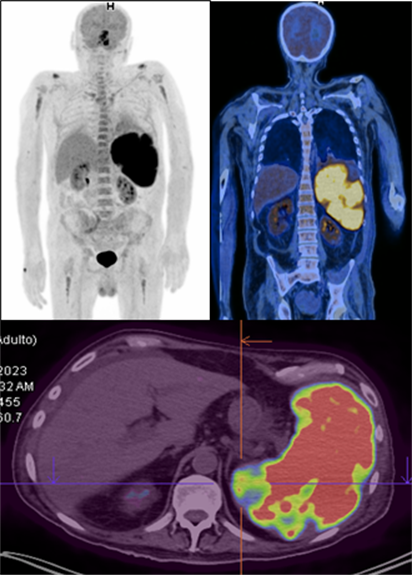

Posterior a un mes, presentó recaída de síndrome hemofagocítico (tabla 1), con necesidad de hospitalización y manejo en terapia intensiva, uso de vasoactivos, transfusión de concentrados de glóbulos rojos y plaquetas. PET CT, con bazo agrandado de tamaño, con importante actividad metabólica del radiotrazador (fluorodesoxiglucosa), acompañado de zonas ametabólicas correspondientes a áreas de infarto y/o necrosis (figura 2).

Figura 2. Tomografía por emisión de positrones (PET/TC) con captación de radiofármaco en bazo.

En el estudio de Ma. J, todos los pacientes mostraron esplenomegalia marcada en la tomografía inicial, además remarcan la importancia del PET-CT como una herramienta útil para identificar la actividad metabólica en el bazo. De igual manera en nuestro caso, el estudio de PET-CT fue determinante tras la recaída del paciente, mostrando una captación intensa de FDG en el bazo con zonas de infarto y necrosis, siendo un indicador clásico de infiltración neoplásica masiva (3).